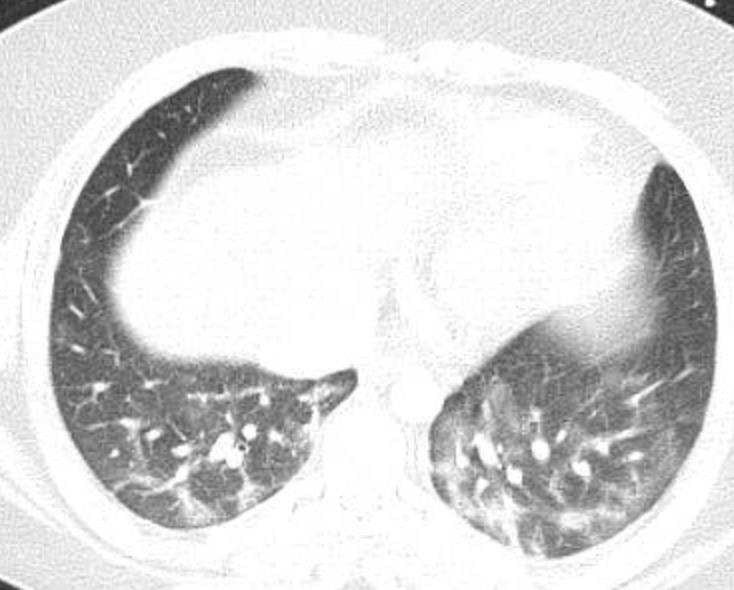

Acute Pediatric COVID-19: CT

21 Imaging of Covid 19 infection in children

3 Phases

Early: "Halo" sign

Local infection

Progressive: Diffuse GGO

Developed: Consolidation

Surr vasc congestion

Inflammation - adj alveoli

Alveoli fill with fluid/cells

Imaging of Covid 19 infection in children

Local infection Surr vasc congestion